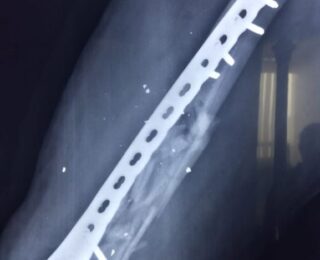

Paciente masculino de 33 años de edad sufre accidente por proyectil de arma de fuego de alta energía (Imagen 1) el cual afecta gravemente el fémur derecho. Como primer procedimiento se realiza una colocación de un fijador externo (imagen 2), y posteriormente se interviene para la fijación interna por medio de una placa LCP (Imagen 3 y 4). Se espera que la recuperación sea en los próximos 3 a 4 meses y que haya una integración de los injertos.

Tratamiento con placa LCP, logrando una excelente reducción.